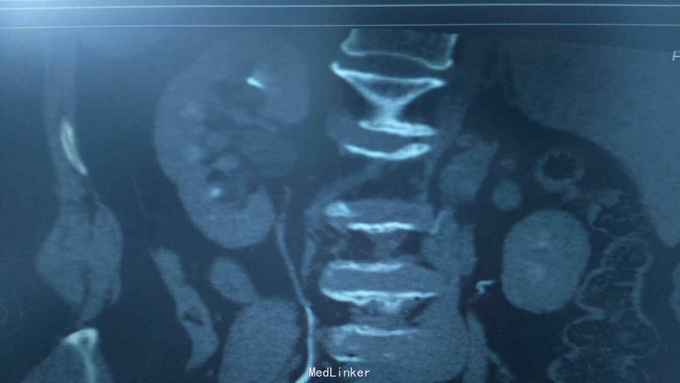

68岁,女性。 主诉:左侧腰痛1年,加重1个月。 病史:1年前无明显诱因出现左侧腰痛,无恶心呕吐,无肉眼血尿。1个月前加重,于外院查泌尿系彩超显示:左肾积液,输尿管显示不清。

诊断:双肾盂旁囊肿 治疗:因患者肾盂未明显受压,疼痛症状不明显,等待观察,暂未予处理。

双侧同时出现的病例并不多见,临床只能通过泌尿系统CTU或增强CT加以鉴别,彩超无法区分肾盂积水及盂旁囊肿。